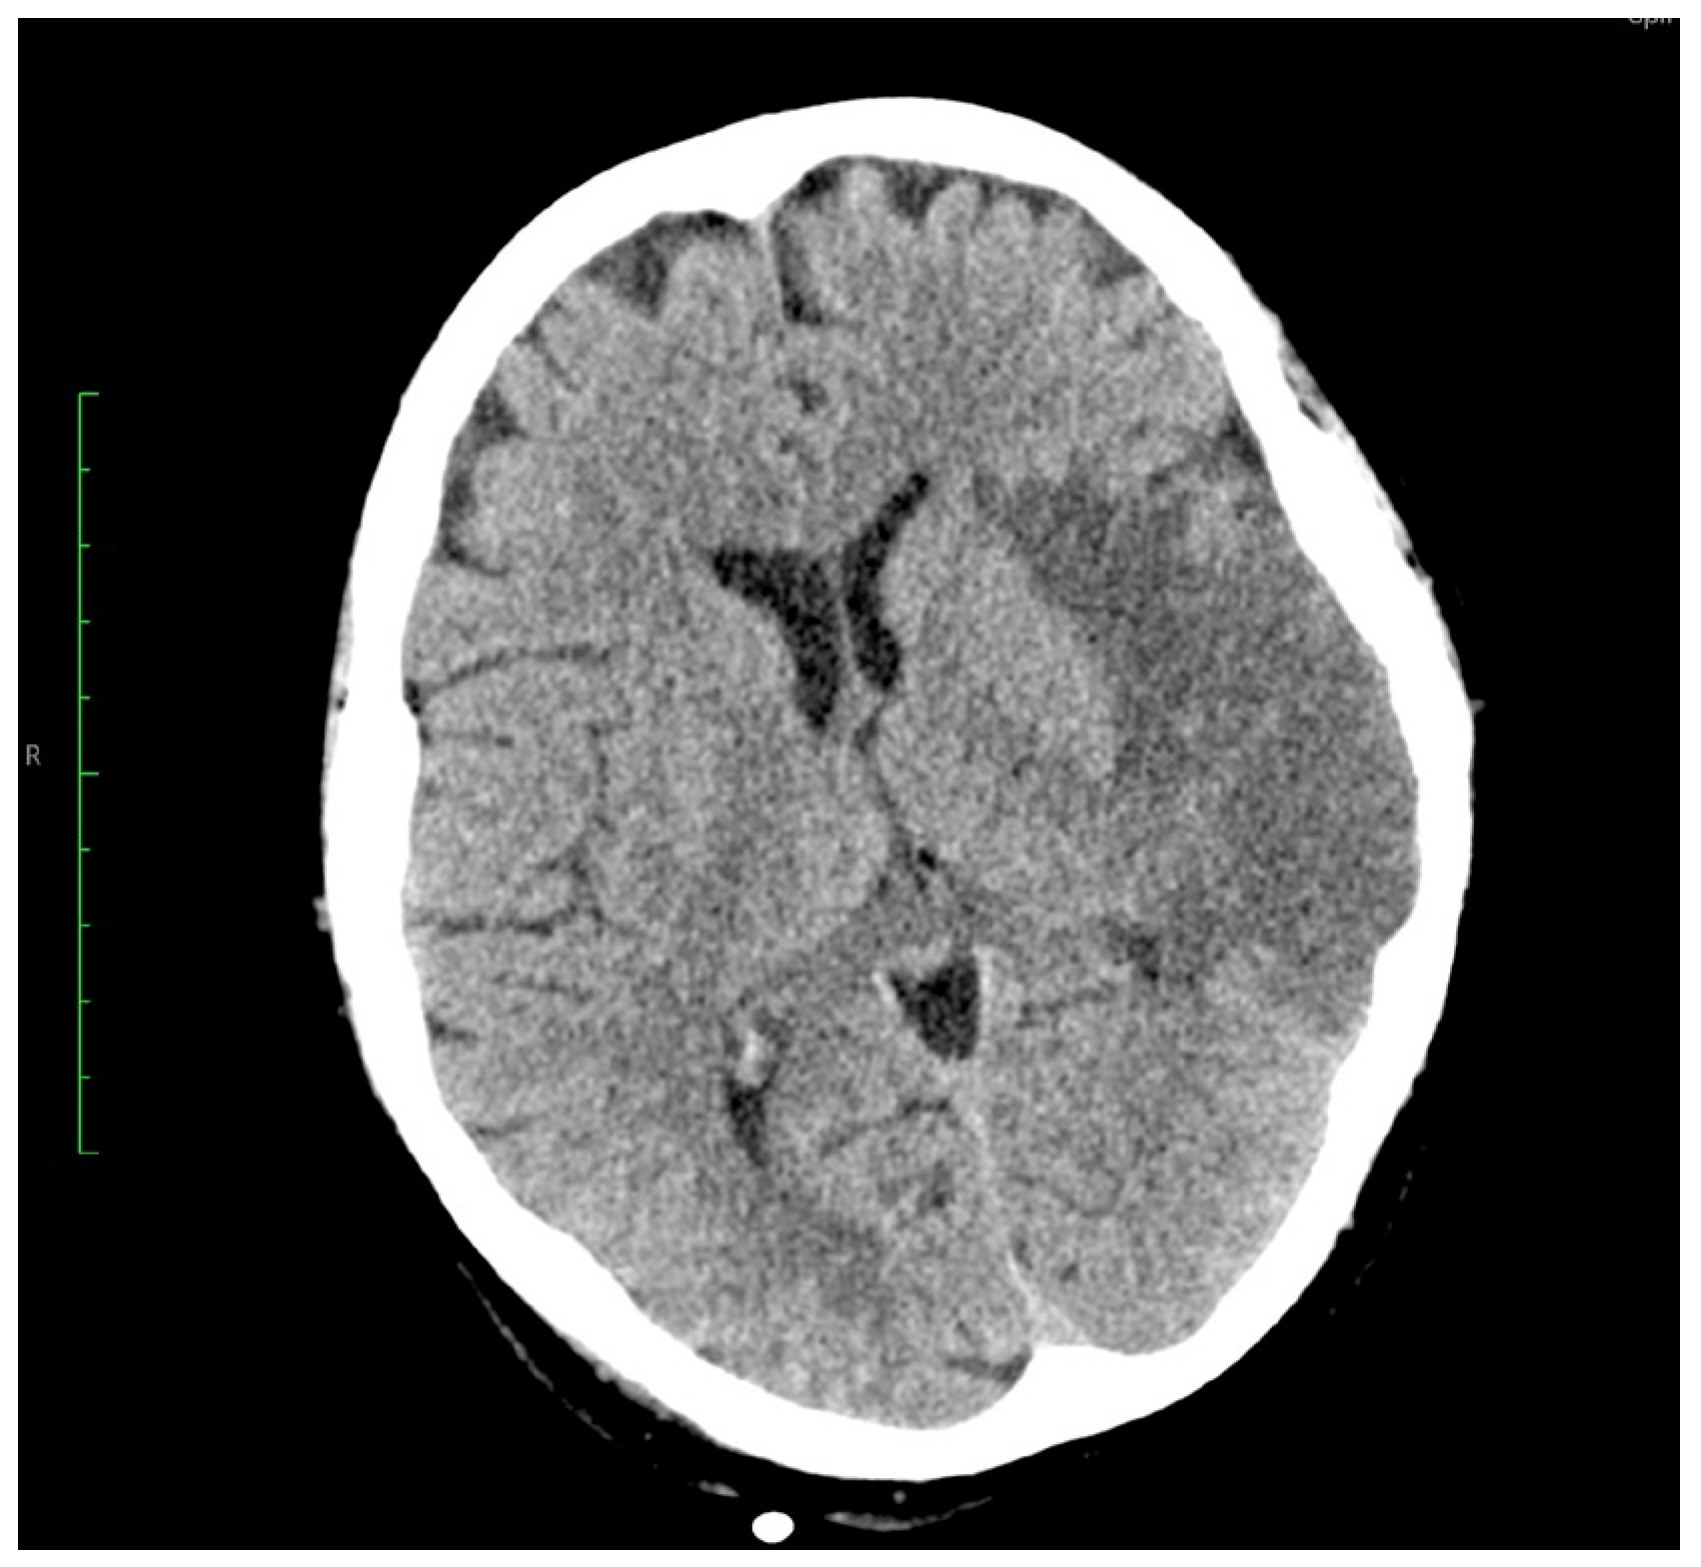

Rare Case of Grade 3 Undifferentiated Pleomorphic Sarcoma in Left Atrium, Mitral Valve, and Papillary Muscle

2. Case Report

3. Outcome and Follow-Up